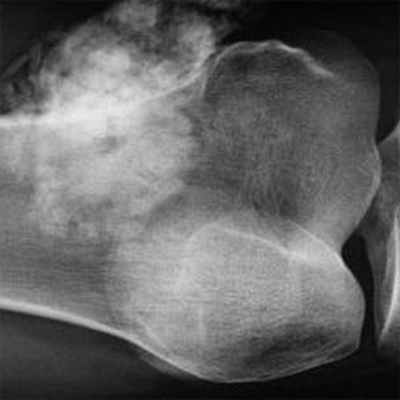

• Рентгенография обычно позволяет выявить литическое образование. Некоторые опухоли молочной и предстательной желёз на рентгенограммах представлены бластическими образованиями •• Остеолиз визуализируется рентгенологически при разрушении 40–50% костной ткани и достижении размеров более 1 см, сопровождается гиперкальциемией и экскрецией содержащих гидроксипролин пептидов •• Остеобластические повреждения выявляют при радионуклидном сканировании костей и рентгенологическом исследовании (увеличение плотности кости и склероз). Остеобластические повреждения могут сочетаться с увеличением в сыворотке крови концентрации ЩФ и гипокальциемией.

Рак простаты чаще бывает бластным, рак легкого – литическим, а рак молочной железы может быть бластным или литическим.

У пациентов с переломами, особенно у пожилых людей, важно определить, является ли данный перелом патологическим по причине заболевания раком. Можно заподозрить такой перелом, особенно если у пациента диагностирован первичный рак. Однако перелом может быть первым проявлением рака в другом месте тела. Рентгенографическое изображение может иметь деструктивный характер, что предполагает наличие рака, но может иметь только незначительные аномалии, например, такие как точечные кальцификации, которые легко пропустить и которые могут быть единственными признаками, указывающими на наличие опухоли. Кроме того, хотя это и нетипично, поражение кости, которое считается причиной метастатического перелома, может быть переломом, вызванным первичной опухолью кости, такой как хондросаркома или остеосаркома. Дифференциацию атипичного (возраст пациента или рентгенологический признак) деструктивного «метастатического» поражения с переломом или без него, особенно с наличием точечных кальцификаций, от редкой первичной опухоли кости следует проводить вместе с онкологом или рентгенологом, специализирующемся на мышечно-скелетных патологиях.